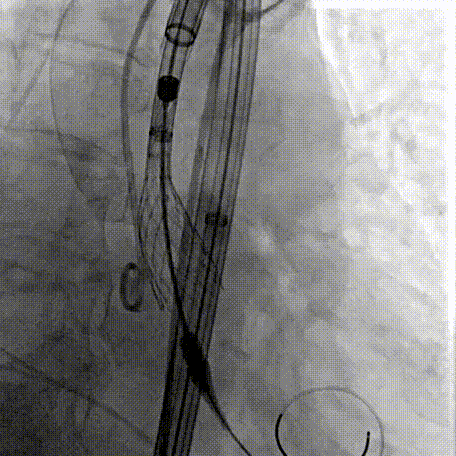

Step 2.建立大鞘通路:大鞘通过升主、边进入边加弯,避免剐蹭弓部斑块

过弓示意图

手术中其实有个关键点,在可调弯鞘过弓的时候,我们特意放慢了速度,一遍进一遍调弯,确保每一步都不触碰弓顶钙化。这台手术的成功,本质上是 “病变特点和器械特性” 的精准匹配。对同类型来说,碰到瓷化升主动脉合并复杂弓的病例,建议术前一定要把钙化范围、弓部角度这些解剖细节分析透,器械选择上不用局限于单一方案,多考虑协同作用,或许能找到更安全的路径。毕竟对我们来说,每台复杂手术的目标都一样:在保证安全的前提下,给患者带来最好的长期获益。